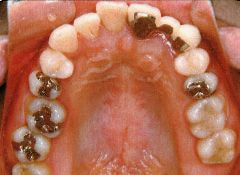

治療例1 (インプラント補綴+矯正)